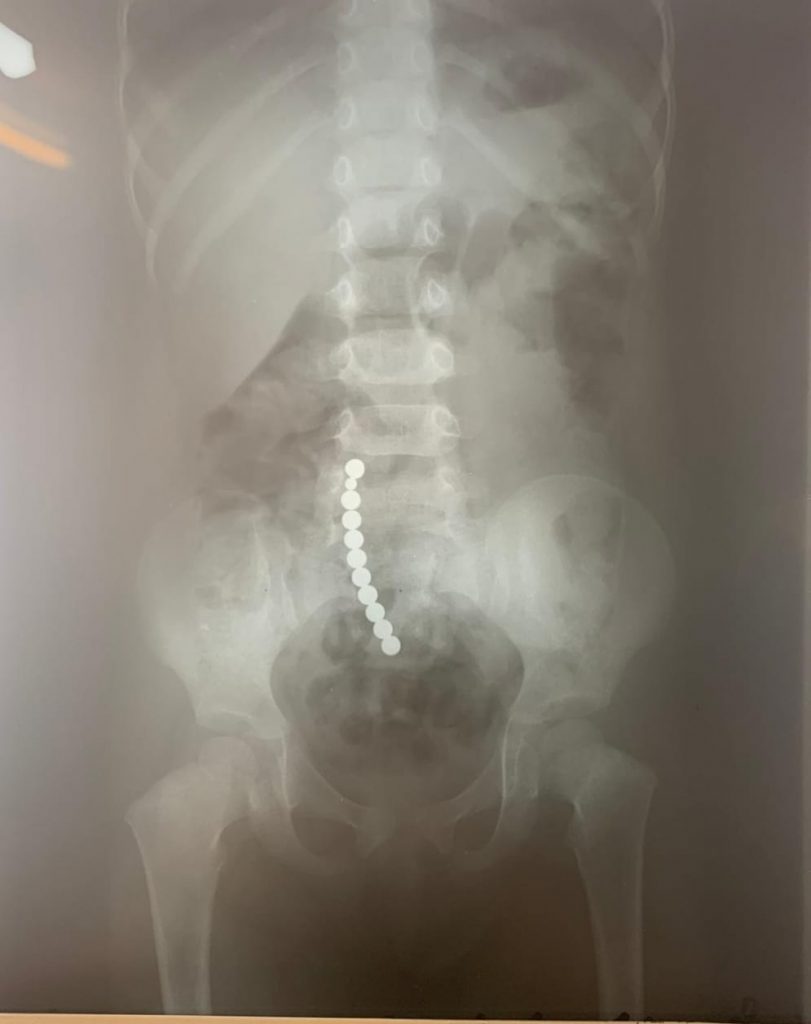

„Acești magneți sunt foarte puternici, iar ingestia lor poate duce la probleme gastrointestinale grave. Odată înghițiți sunt atrași unul spre altul chiar dacă se găsesc în secțiuni diferite ale tubului digestiv. O ansă intestinală prinsă între acești magneți se poate perfora ducând la tratament chirurgical de urgență. În secția noastră, de la începutul anului s-au prezentat trei cazuri, două fete și un băiat, cu vârste cuprinse între 2 și 4 ani. Aceștia au suferit perforații la nivelul intestinului subțire și au necesitat intervenții pentru îndepartarea porțiunii de intestin afectate” – a precizat dr. Adriana Constantineanu.